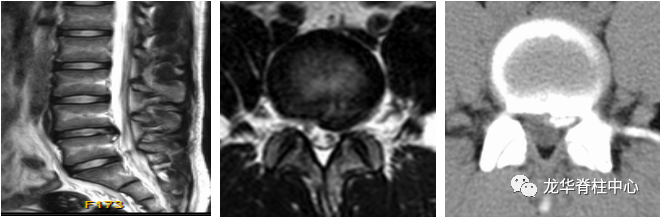

15岁的小王同学,在其母亲陈女士的陪同下来就诊。小王说,最近1月余来总感觉腰痛和左腿痛,一走路就加重,根本无法正常走路,呈跛行步态,陈女士见自己儿子小小年纪就这般难受,现在又是疫情期间,不知道如何是好,焦虑之际,经介绍,前来我院就诊,张昊主任医师予仔细、全面的查体,并阅读了相关影像学资料,经过团队的讨论,首先明确诊断为 “腰椎间盘突出症(L4/5 左侧)”。

针对该患者的诉求,张昊主任与其团队进行了反复的讨论并分析小王的问题,首先,小王才15岁,但腰椎间盘突出明确并伴有椎体后缘离断,神经受压明显,导致下肢疼痛、麻木,严重影响日常生活和学习,经过一段时间保守治疗,仍反复,并且越来越明显了,因此针对青少年的腰椎间盘突出症患者治疗方面该如何定夺呢?张昊主任分析,结合该患者的特殊性,又要考虑患者以后的影响,把相关治疗方案以及相应的风险等事宜详细告知陈女士,最终在微创理念下采用脊柱内镜下腰椎间盘摘除技术为小王进行手术,手术切口1cm,术后症状缓解,恢复良好,效果非常满意,第二天顺利出院。

术前影像